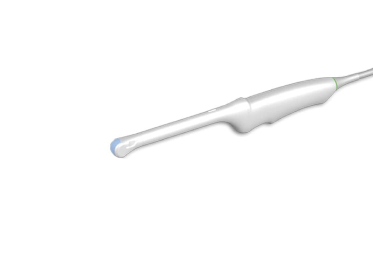

— мультичастотные УЗ-датчики: линейный датчик Edan L742UB, конвексный датчик Edan C352UB, фазированный датчик Edan P5-1b

— конвексным C352UB: частотный диапазон датчика 2–6 МГц, угол обзора 70°, глубина сканирования 320 мм, количество элементов 128

— трансвагинальный датчик Edan E612UB

- Датчик конвексный ультразвуковой C352UB — 1 шт.